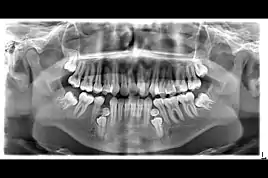

Si bien un solo exceso de diente es relativamente común, la hiperdoncia múltiple es rara en personas sin otras enfermedades o síndromes asociados. Muchos dientes supernumerarios nunca entran en erupción, pero pueden retrasar la erupción de los dientes cercanos o causar otros problemas dentales o de ortodoncia. Los dientes adicionales de tipo molar son la forma más rara. Las radiografías dentales a menudo se usan para diagnosticar la hiperdoncia.